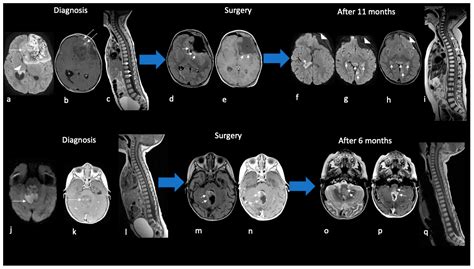

Diagnosis typically begins with advanced neuroimaging, such as MRI scans with and without contrast, to visualize the tumor's size and location. However, imaging alone is rarely sufficient. A definitive diagnosis is achieved through a surgical biopsy or total resection, followed by a rigorous pathological examination. Pathologists look for the loss of INI1 protein expression in the tumor cells, which serves as a molecular hallmark for an Atypical Teratoid Tumor.

• Atypical Teratoid Rhabdoid Tumor MRI